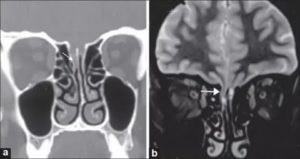

- Эндоскопическое исследование носа и околоносовых пазух (на рисунке — эндоскопия полости носа прямым эндоскопом; в проекции задней стенки клиновидной пазухи виден небольшой костный дефект, через который поступает ликвор).

- Компьютерная томография (КТ) основания черепа и околоносовых пазух (на рисунке определяется большой дефект основания черепа в проекции ситовидной пластинки с формированием менингоцеле (показано стрелкой)).

- Магнитно-резонансная томография (МРТ) – дополнение к КТ для исключения менингоэнцефалоцеле.

Источник назальной спонтанной ликвореи на МРТ головного мозга с контрастированием (показан белой стрелкой).